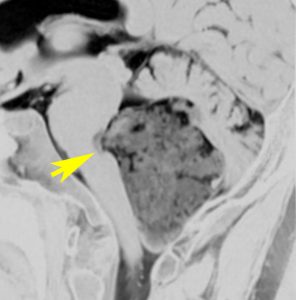

小脳橋角部の典型的な類表皮のう胞 epidermoid cyst

20代の女性が右の激しい顔面痛(三叉神経痛)で発症しました。左から順にMRIのT1強調画像,T2強調画像,拡散強調画像です。髄液と同じように見えますので脳の形の変形だけで腫瘍があることを疑います。でも,拡散強調画像では真っ白になるので腫瘍が存在していることがわかります。三叉神経は腫瘍の真ん中にあって伸びています。

術後の写真です。普通のMRIでは全部取れているかどうかわかりませんが,左の拡散強調画像をみるとおよそ全部取れていることがわかります。でも完全摘出の完全な証明は画像ではできません。術後10年くらい経ちますが再発はありませんでした。